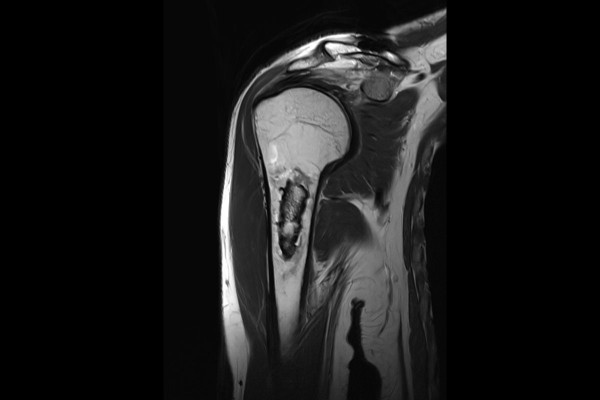

MRI를 확인했을 때 역시 주변 뼈와 다른 신호가 뼈 안에서 관찰되는데, 이런 경우에는 조영제를 포함한 MRI 촬영을 하게 됩니다.

조영제를 포함한 MRI 검사 결과, 종양 주변과 안쪽부분이 조영증강 된 것이 확인되었습니다. 이 경우에는 영상의학과와 협진이 필요하여 다학제 협진을 진행하였고, 골괴사나 내연골종 혹은 골내 지방종, 마지막으로 가능성이 매우 드물지만 저등급의 연골육종이 의심되었습니다.